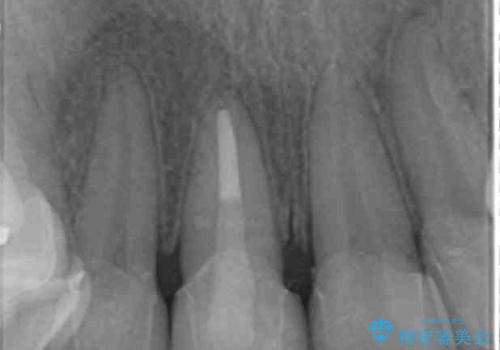

右上1番は、根の治療のやり直しをしています。

- 63.8万円(右上4~左上2:emaxクラウン 7万円x6本、仮歯 1万円x6本、歯周外科手術 15万円、右上1:精密根管再治療 9万円およびファイバーコア2万円)費用は治療当時の料金となります